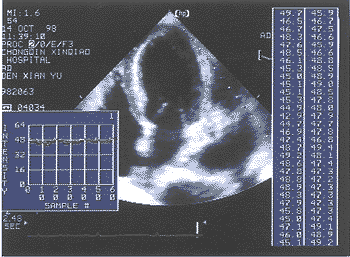

仪器采用美国HP SONOS 5500型超声诊断仪,该机配有完整的AD-IBS联机采样分析软件,含有动态磁光盘记录系统,探头频率为2~4MHz 。常 规检查心脏结构,测量各腔室大小、室壁厚度、心肌重量、二尖瓣血流、左室收缩及舒张功 能参数。在获得标准的乳头肌水平左室短轴和心尖四腔心切面的二维图像后,将仪器调至AD -IBS功能状态,固定仪器设置,包括深度、增益、TGC及LGC,在整个研究过程中保持不变 ,联机采样时固定感兴趣区域的取样框(椭圆形,21×21Pixel),分别置于左室短轴切面的 前壁、前间壁、后间壁、后壁、侧壁、左室腔及四腔切面的二尖瓣环部、室间隔中部(图1) 、左室腔中间(图2)取样,取样跟踪时尽量避开心内、外膜信号的干扰。分析结果包括3项参 数(单位:dB):PPI(峰值-峰值的密度)、AII(平均密度)、SDI(密度标准差)。定量结果可综 合显示在表中(图3),或以坐标图同时显示1~3条定量曲线(图4)。

图1 室间隔中部检测取样及结果显示